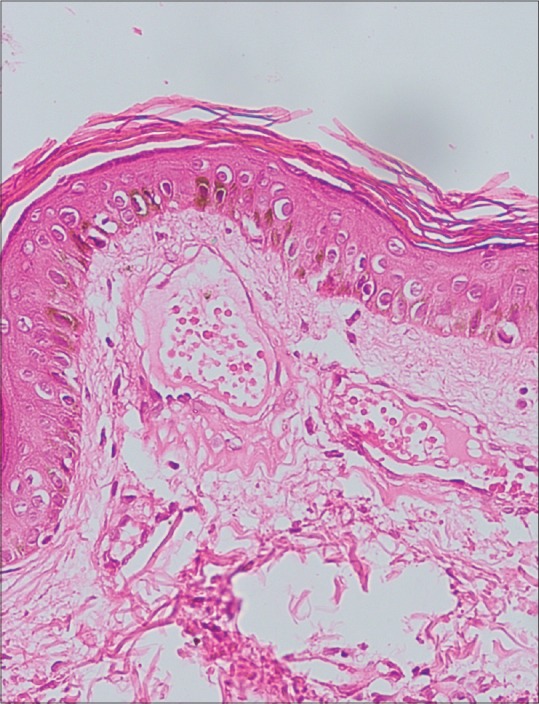

Routine hematological, biochemical, serum estrogen, and testosterone levels were normal. Histopathology revealed presence of multiple dilated capillaries with normal endothelial lining in the papillary and superficial reticular dermis [Figure 3]. There were neither epidermal changes nor extravasation of red blood cells. Based on the clinical, dermoscopic, and histopathological features, she was diagnosed as a case of blaschkoid angioma serpiginosum (AS). The patient was counseled regarding the benign nature of the disease and advised pulsed dye laser (PDL) treatment.

Figure 3.

(H and E, ×40) Histopathology revealed presence of multiple dilated capillaries with normal endothelial lining in papillary and superficial reticular dermis